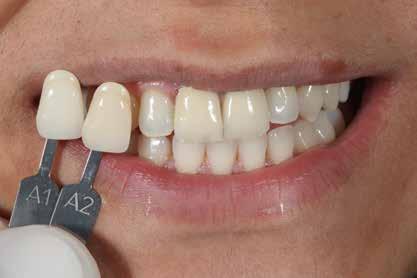

A szakirodalomban fellelhető eredmények alapján kerámia héjak ragasztására a kontaminációtól mentes, frissen vágott zománc felszín a legalkalmasabb. A hosszú távú sikeresség elérésének további feltétele a fogak konzervatív módon történő preparálása, továbbá a ragasztás kofferdám felhelyezésével biztosított, abszolút izolálásban történő kivitelezése. Úgy véljük, hogy a fenti faktorok biztosították a cikkben bemutatásra kerülő esetek – 5 évvel az átadás után megfigyelhető – sikerességét. A kofferdám izolálás alkalmazása számos előnyt biztosít a gyakorló fogorvos számára. Megakadályozza a munkaterület nyállal, vérrel, vagy szulkusz-váladékkal történő kontaminációját, és javítja a kezelendő területre való rálátásunkat. A fogak kerámia héjak ragasztása előtt történő izolálása azonban gyakran kihívást jelenthet a kevesebb klinikai tapasztalattal rendelkező fogorvosok számára. Jelen esetbemutatásban ismertetjük a kofferdám felhelyezésének lépéseit és néhány olyan gyakorlati tanácsot, amelyek jelentősen megkönnyíthetik a munkánkat, azokban az esetekben, amikor a második kisőrlőfogak közti területet kívánjuk kofferdám segítségével izolálni. A kofferdám kapcsok segítségével került rögzítésre, majd fogakat körülvevő széleit óvatosan az ínybarázdába forgattuk. A kerámia héjak számára előkészített fogakra ragasztás előtt egyenként kapcsokat helyeztünk annak érdekében, hogy a kerámia héjak rögzítése ideális körülmények között történhessen. A lépések részletes ismertetése segítséget jelenthet – a kevesebb klinikai tapasztalattal rendelkező fogorvosok számára – az abszolút izolálás megvalósításához szükséges lágyrészmenedzsment megértéséhez. Ezek az ismeretek rendkívül hasznosak lehetnek, ha a jövőben a kerámia héjak ragasztását megfelelő módon megvalósított kofferdám izolálás mellett kívánják kivitelezni. A cikkben ismertetett módszerek alkalmazásával az abszolút izolálás megvalósítható, a gumilepedő – vérzés nélkül – ínybarázdába történő beforgatására, és a ragasztáshoz szükséges idő csökkentésére.

A rendelésünkön egy 34 éves latin-amerikai nőbeteg azzal a panasszal jelentkezett, hogy a fogait „túl rövidnek” találja, és ezen felül a mosolyával sem volt megelégedve. Az anamnézisfelvétel alapján egészséges volt, elmondása szerint rendszeresen járt orvoshoz. Öt évvel korábban néhány hátsó fogát restaurálták. Páciensünk szájhigiénéje megfelelő volt,

a fogait rendszeresen ápolta. House klasszifikációja szerint, amely a pácienseket a fogászati kezelésekhez való attitűdjük szerint négy csoportba sorolja, a páciensünk a szabálykövető csoportba tartozott.

Az előzetes állapotfelmérést és a kezelés megtervezését követően a fogakat minimál invazív módon preparáltuk (1. a-b ábrák), majd az előkészített fogak ínybarázdáiba fonalbehelyező eszköz segítségével (113 Serrated Gingival Cord Packer, Hu-Friedy, Chicago, Illinois) teflonszalagot helyeztünk (Loctite Thread Seal Tape, Henkel Loctite Corp., Egyesült Államok), (1. c ábra). A hagyományos retrakciós fonalak helyett, a rugalmasságuk miatt előnyösebbnek tartjuk a teflonszalagok használatát. A kofferdámot (Dental Dam, Nic Tone, Bukarest, Románia) az előkészített fogakon kívül, az azoktól disztálisan elhelyezkedő egy-egy fognak megfelelően is perforáltuk.

Az oxigén inhibíciós réteg kialakulásának elkerülése érdekében a kerámiafelszíneket glicerin géllel (Liquid Strip, Ivoclar Vivadent, Schaan, Liechtenstein) borítottuk, majd ezeket a felszíneket ismét 20-20 másodpercen keresztül világítottuk. A végeredmény megfelelt a páciens esztétikai igényeinek (6. a. ábra). Az átadott restaurátumok épségének megőrzése érdekében, a páciens számára éjszakai fogvédő sín készült. Az ötéves kontroll alkalmával megállapítottuk, hogy az elvégzett kezelésünk továbbra is sikeresnek tekinthető (6. b. ábra)